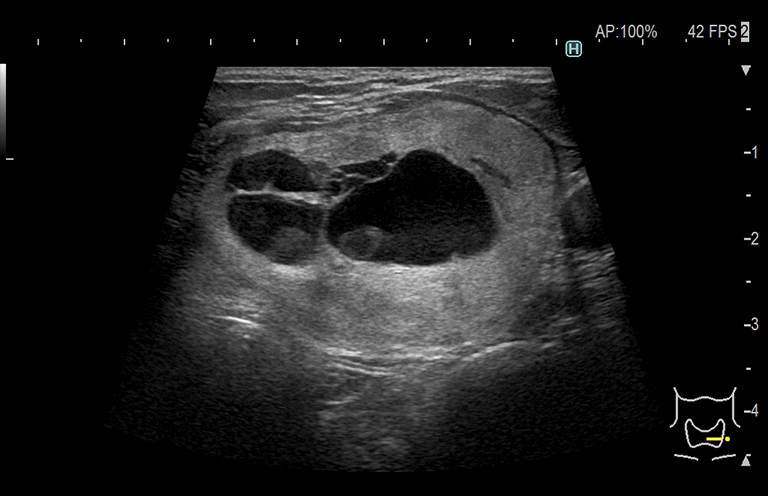

Aplicación: Obstetricia

Función/análisis: Modo B

Comentarios: Feto (13 semanas)

Comentarios: Placenta